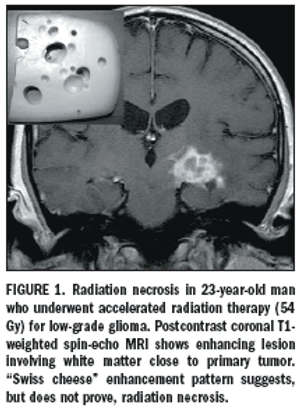

Radiation plays an important role in the treatmentof primary and secondary centralnervous system neoplasms.